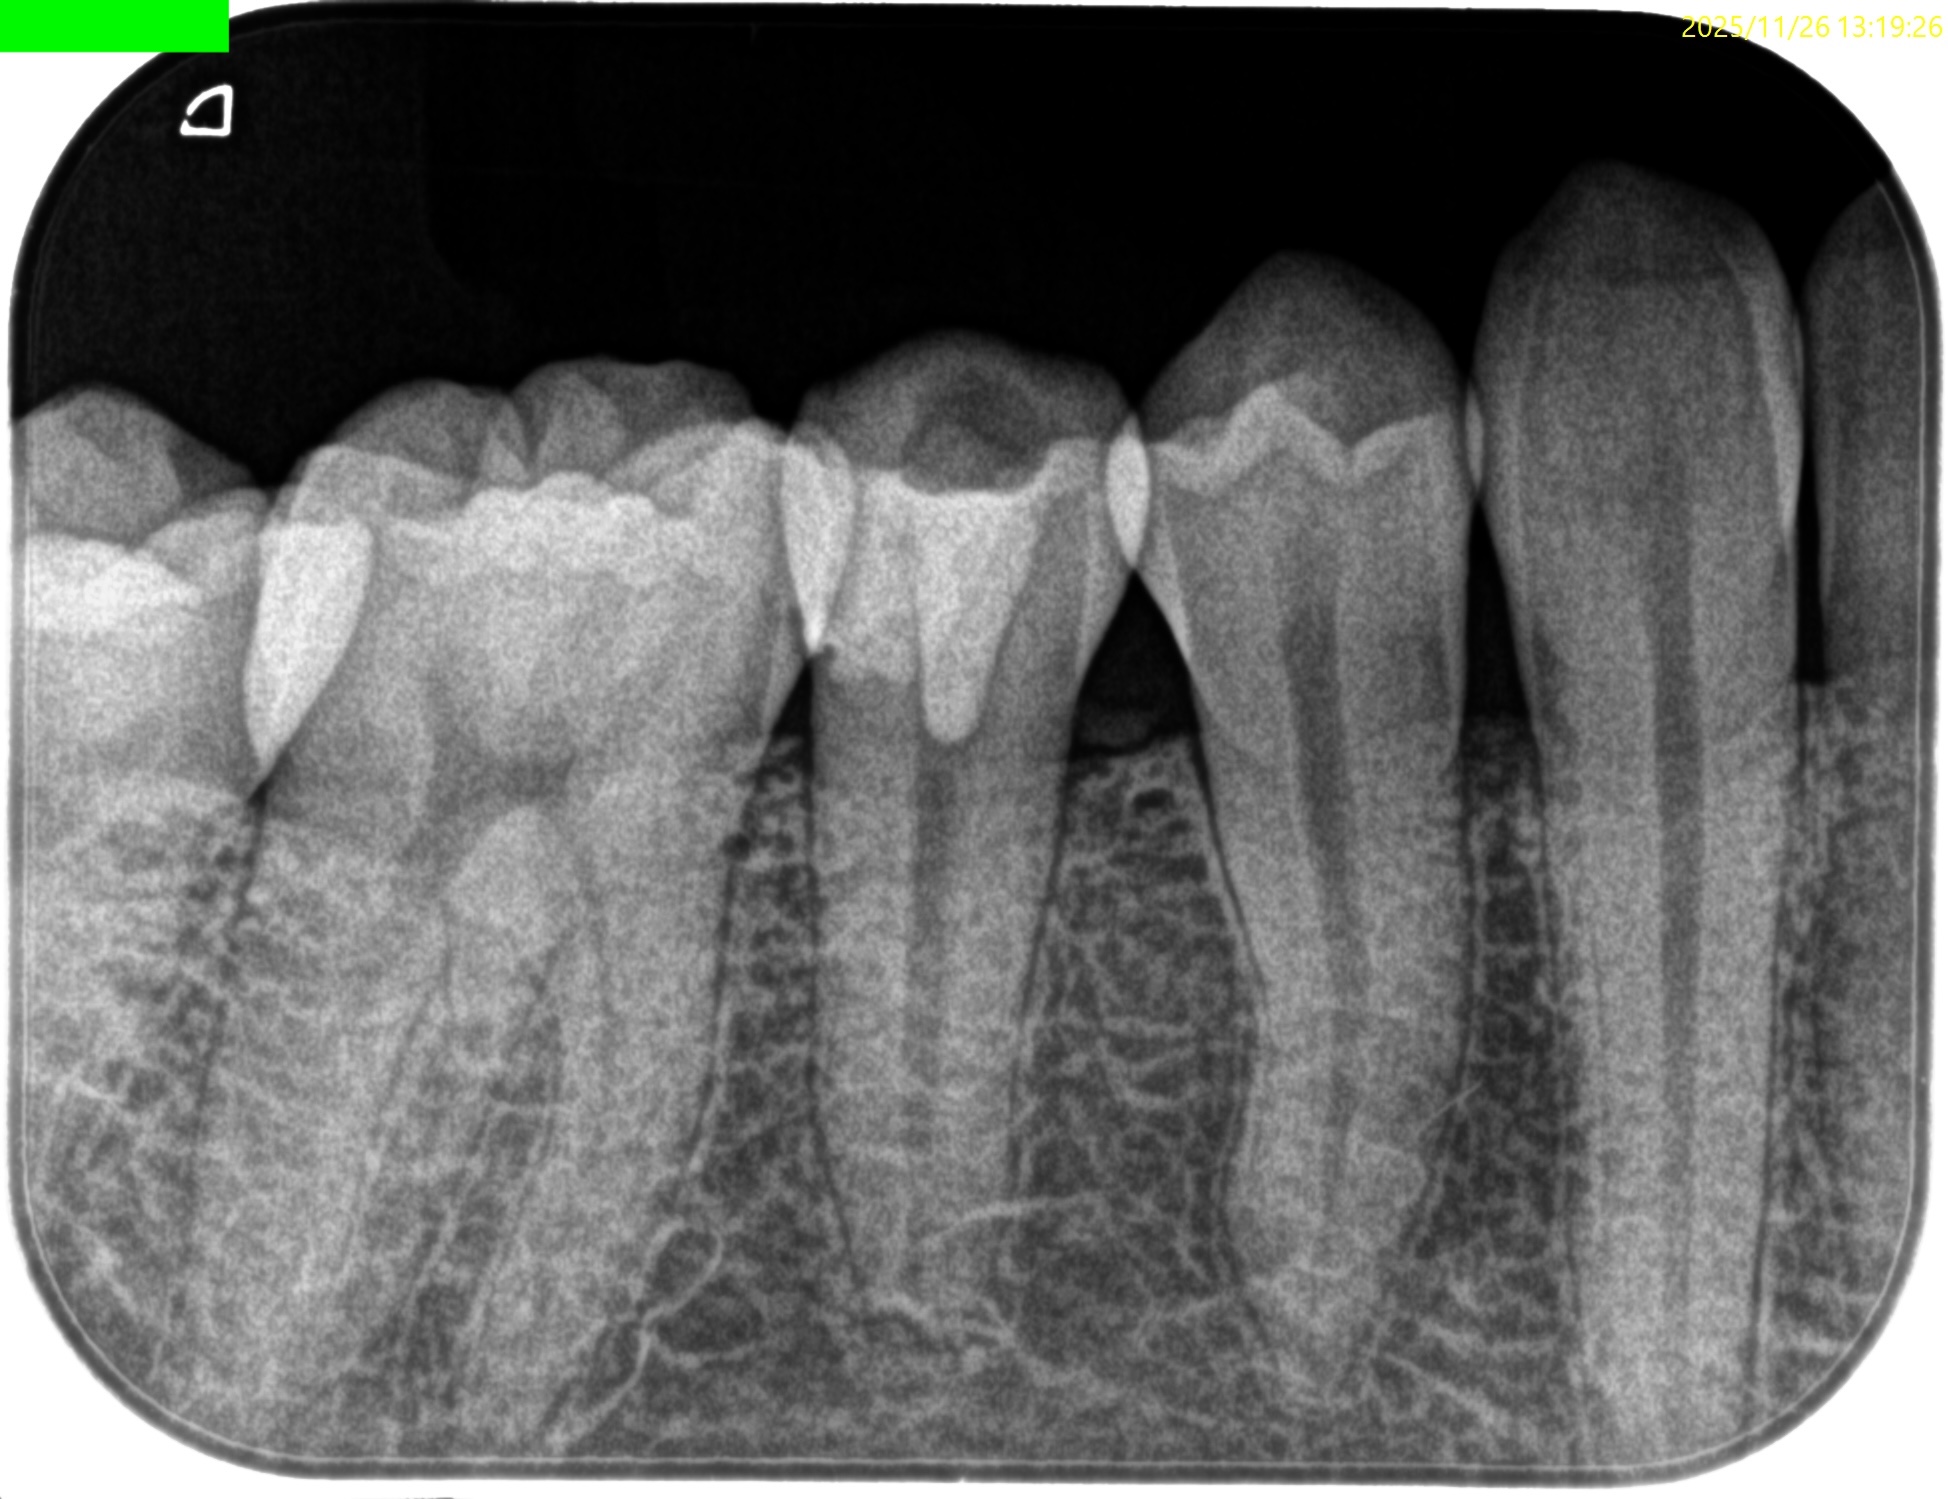

Pre-op Endo test(2025.11.26)

#29に打診痛がある。

紹介元の先生によれば#40.04まで形成したが術後の痛みが続いているという。

根尖病変はない。

根管充填後にPA, CBCTを撮影した。

問題はないだろう。